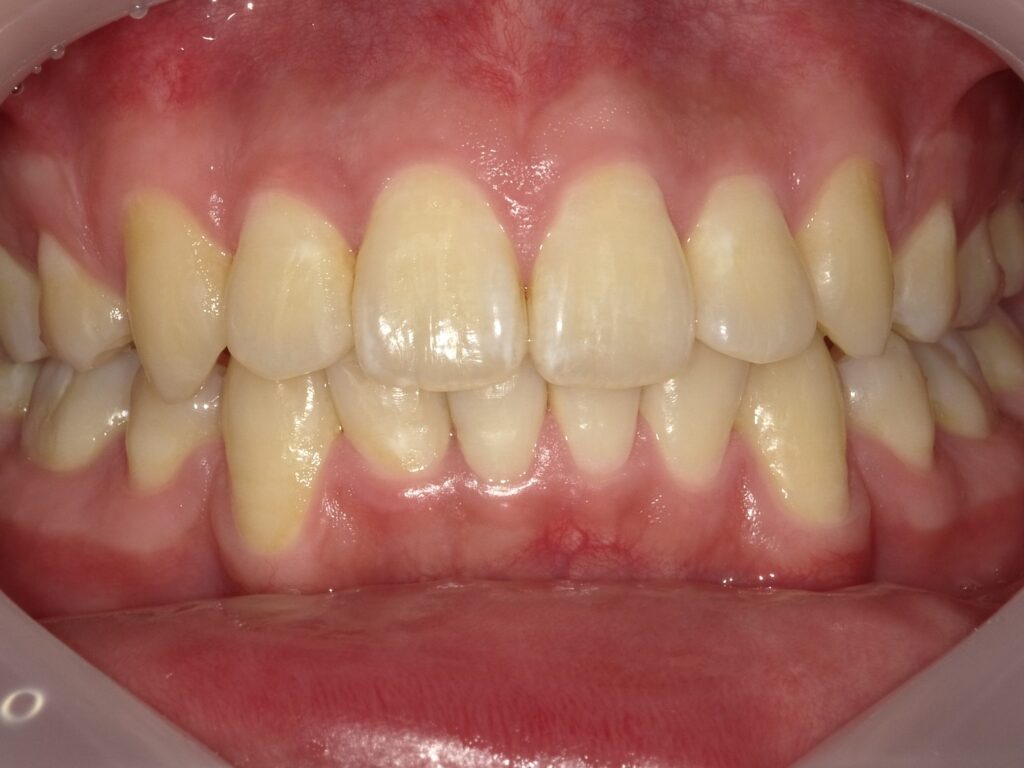

AFTER:2025年

当院でも小児患者さんから診てる子が成人になり、良い口腔内をすっと維持できている人も多数いて来院した患者さんとたまに10年以上口腔内写真やレントゲンの記録を見返して、頑張って口腔管理してる甲斐があったねと共に喜べているのが歯科医師としての幸せになっています。